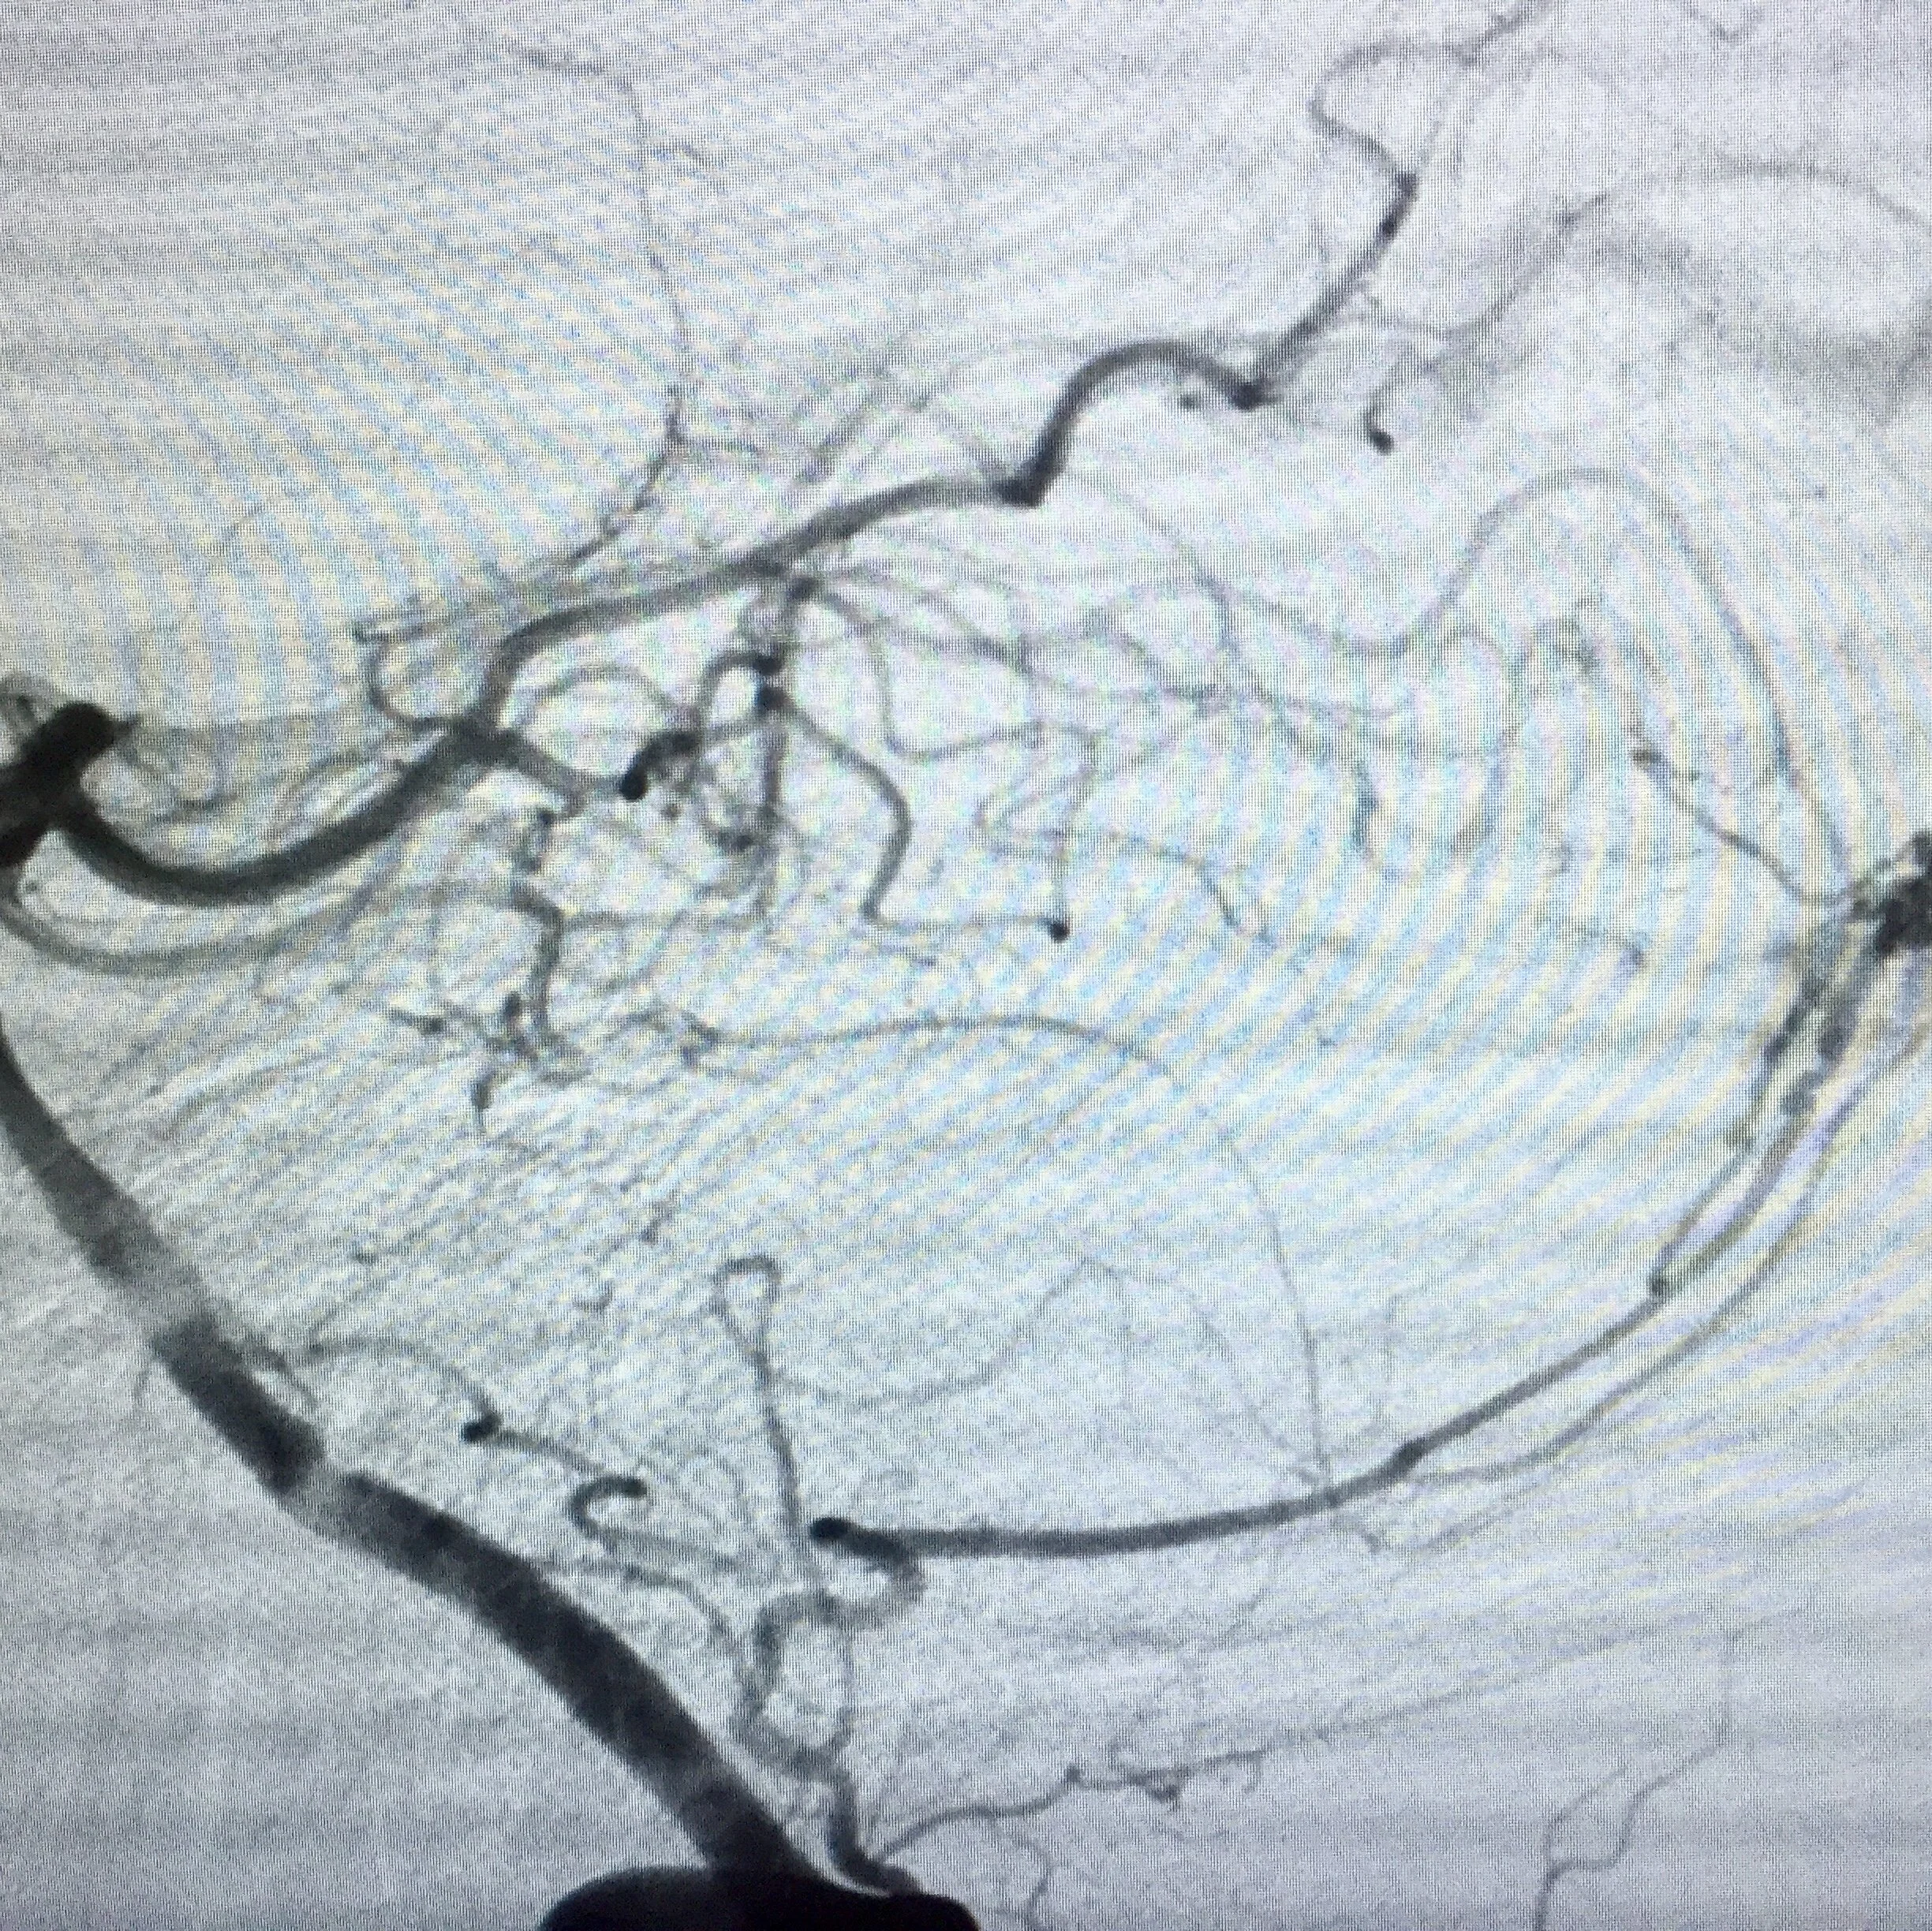

Arteriovenous Malformations (AVM)